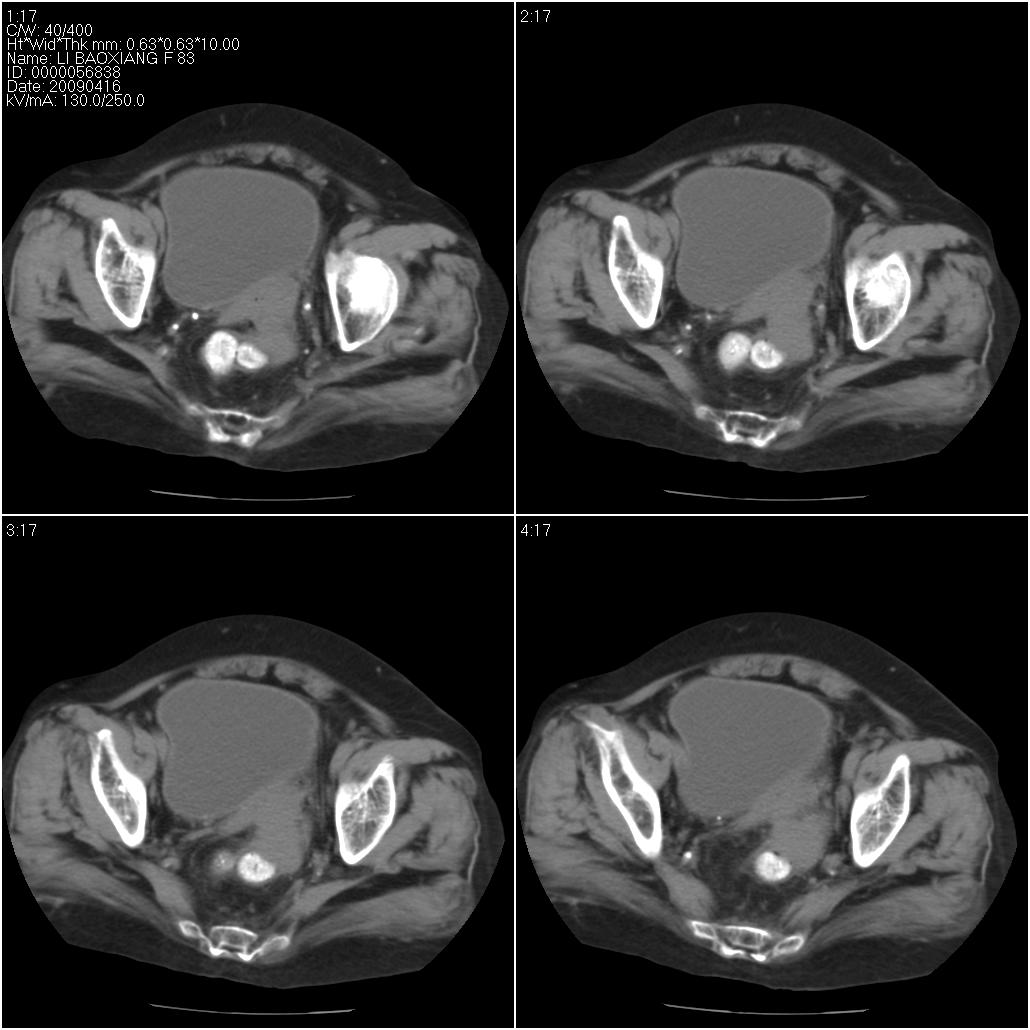

标题: CT19496:女性,83岁。阴道出血多年,患者一般情况良好。 [打印本页]

标题: CT19496:女性,83岁。阴道出血多年,患者一般情况良好。

乙状结肠病变累及子宫,建议结合妇科检查

考虑乙状结肠肿瘤累及子宫;建议行肠镜检查。

考虑:乙状结肠癌累及子宫,建议钡剂灌肠。

乙状结肠癌累及子宫

乙状结肠癌侵犯子宫可能性大。